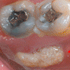

A 58-year-old man receives chemoradiotherapy as definitive management for a T3, N2b squamous cell carcinoma of the tonsil. He returns to clinic for a 6-week post-treatment follow-up visit, complaining of pain in the back of his mouth. Transoral exam is notable for the following finding (red arrow).

What is the most likely diagnosis?